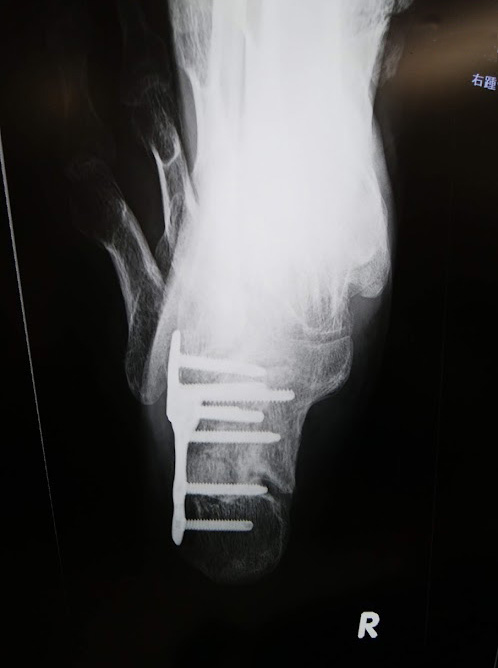

二年半前、私はコレで、右足踵骨を骨折しました。

全治三ヶ月、入院期間一ヶ月少々でした(´;ω;`)でも、死ななかったのが不幸中の幸いでした。 pic.twitter.com/MM9BHy2SIm